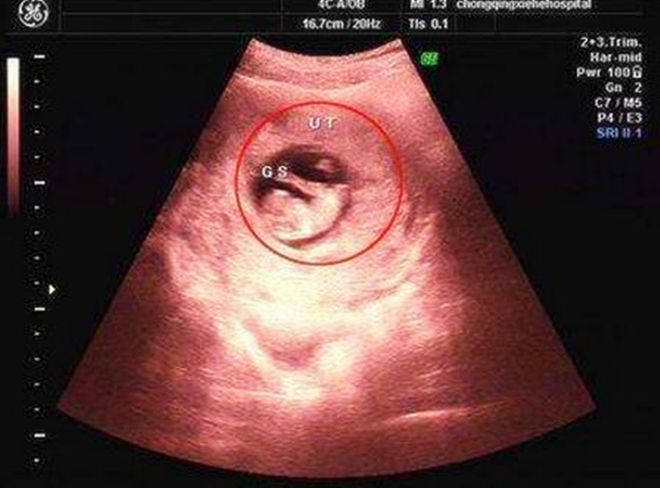

症状,如果发生胚胎停育,孕母的一切妊娠反应都会逐步消失。首先是不再有恶心、呕吐等早孕反应,乳房发胀的感觉也会随之减弱。然后阴道会有出血,常为暗红色血性白带。最后还可能出现下腹疼痛,排出胚胎。上述表现因人而异,有的甚至一点迹象都没有,就直接出现腹痛,然后流产,或胚胎停育后无症状通过常规B超检查发现。大多数孕妇胎儿停止发育后无明显症状,部分孕妇可能见红,一般无腹痛,这与先兆流产不同。

病人有停经史,无论有无见红,在孕早期均应行B超检查,以免漏诊胚胎停育。B超监测胚胎,胎儿发育,如≥6周无妊娠囊,或虽有妊娠囊但变形皱缩,当妊娠囊已≥4cm却看不到胎芽,胎芽的头臂长度≥1.5cm却无胎心博动,即可判定胚胎或胎儿发育异常。后三种情况可以诊断为胚胎停育。另外血β-hcG测定也有助于胚胎停育的诊断。如≥5周,血β-hcG100IU/L;≥6周,血β-hcG2000IU/L,m提示绒毛膜促性腺激素分泌不足,动态观察其值不再上升者,则可判定绒毛上皮衰退,胚胎异常。